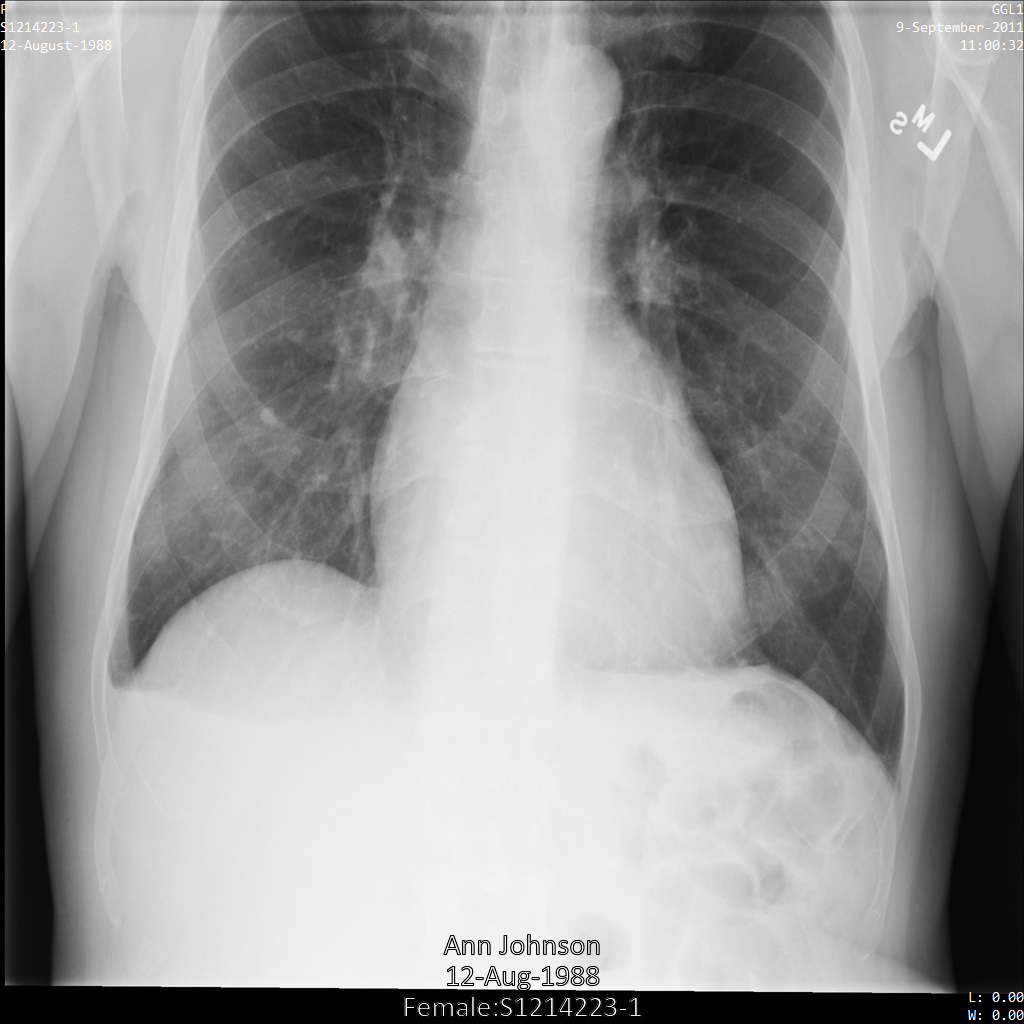

Después de enviar la imagen a la API de Cloud Healthcare mediante el perfil de filtro de etiqueta ATTRIBUTE_CONFIDENTIALITY_BASIC_PROFILE, la imagen aparece de la siguiente manera. Mientras se ocultan los metadatos que se muestran en las esquinas superiores de la imagen, permanece la PHI quemada que se encuentra en la parte inferior de la imagen.

Para quitar también el texto grabado, consulta Cómo ocultar el texto grabado de las imágenes.